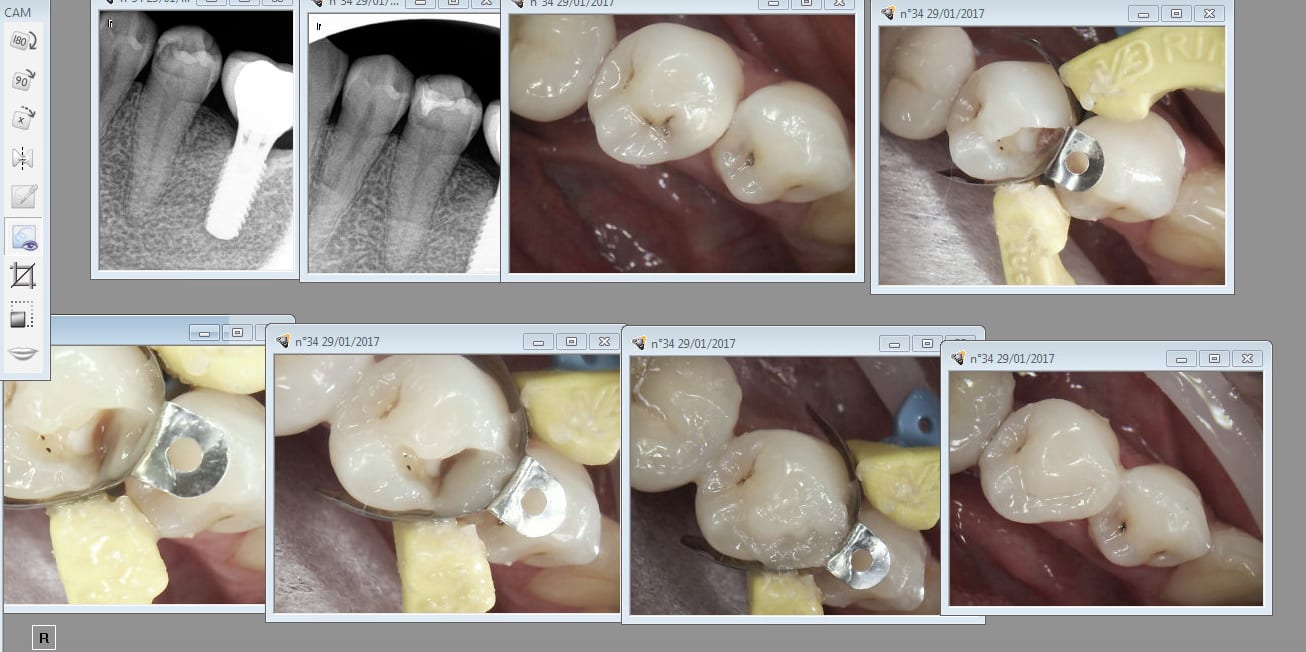

Re essai bulk fill estelite flow

Capture d écran 2017 02 07 19.15 - Eugenol

Estelite bulk fill flow , seringue acide, peak universal bond, fraise diamentée olive pointue, ca allège considérablement la sté et vous avez le composite du pauvre que la sécu paye à tous ses assurés meme riches.

Capture d écran 2017 02 23 12.58 - Eugenol

Non en 2 fois. Tu fais une remontée de marge d'abord. Et au lieu de faire un onlay tu continues. -))))